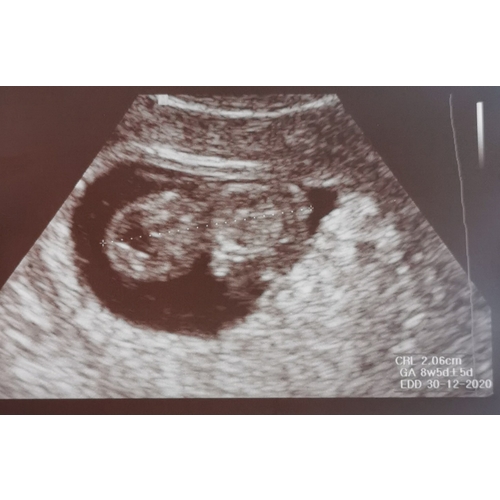

Dit was de mijne met 8+5 😍